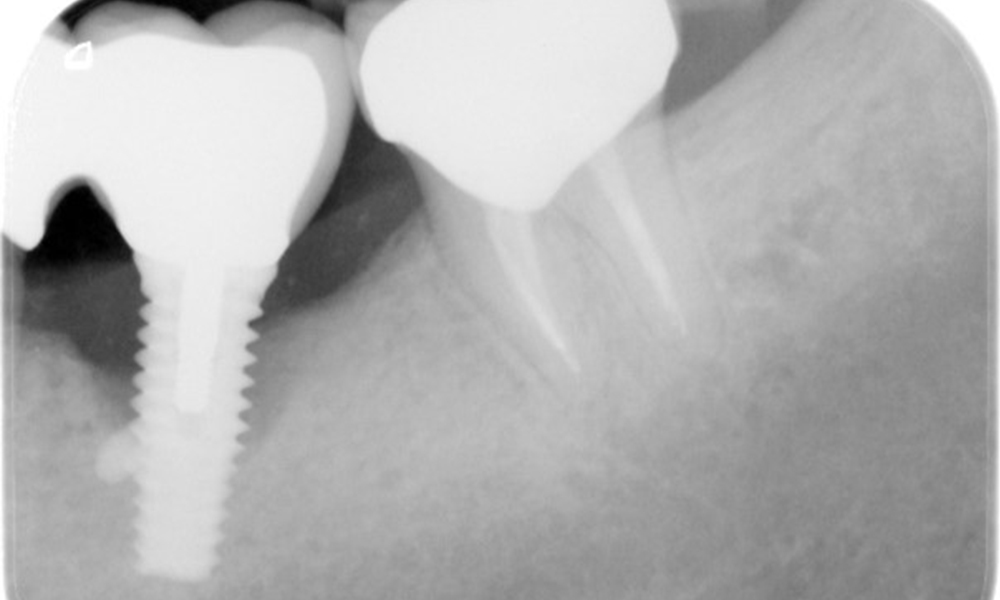

The patient has no particular risk factors with specific dental implications in his medical history. The key factor, therefore, is the requirement in terms of oral health. In this respect, there is evidence of a probing depth of 5 mm at the implant in the 3rd quadrant and, on the X-ray image, increased bone loss. The patient also has currently stable early periodontal disease and two active initial carious lesions.